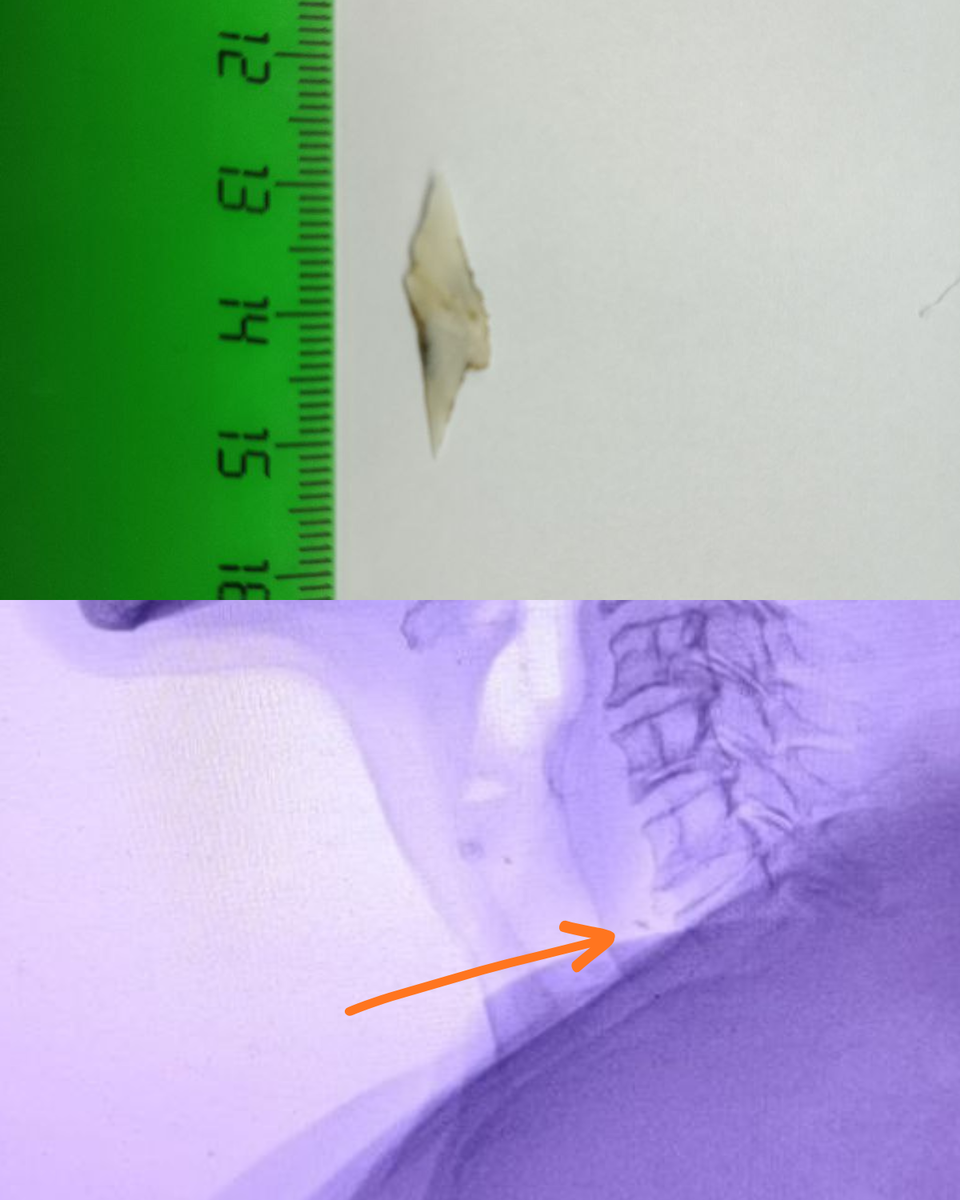

Слаборентгенконтрастное инородное тело в проекции шейного отдела пищевода

В проекции тени пищевода слаборентгенконтрастное инородное тело (рыбная кость?) на уровне межпозвоночного диска в проекции С6-С7.

📝 Действительно, осетровые — хрящевые рыбы, инородное тело либо рентгеннеконтрастное, либо малоконтрастное. Срок возможного нахождения инородного тела — около суток. Соответственно локально должно быть воспаление и отёк, а значит увеличение в объеме или толщины органа (если вести речь о двумерном изображении). Серьги ни при чем, они в стороне от инородного тела. Ищем воздушный столб верхних и нижних дыхательных путей (№1). Далее ищем надгортанник и основание надгортанника (№2). В этой зоне между воздушным столбом и позвоночником — устье пищевода (№3). Ниже между воздушным столбом и позвоночником — проекция шейного отдела пищевода (№4), в её проекции и ищем признаки инородного тела. В данном случае расширена тень пищевода, она практически равна толщине воздушного столба трахеи. Это признак локального воспаления и отёка. В проекции тени пищевода на уровне межпозвоночного диска С6-С7 — слаборентгенконтрастное инородное тело (№4).